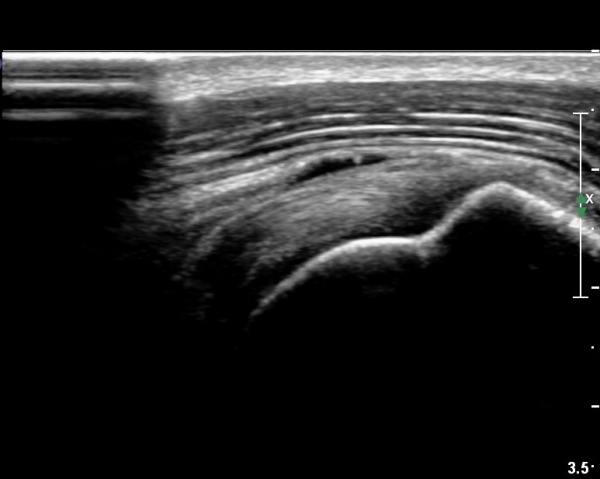

ÃÊÀ½ÆÄ ¼Ò°ß :  È¸Àü±Ù°³°£°Ý °Ë»ó»ó ±Ø»ê°ÇÀº Á¤»ó¼Ò°ßÀ» º¸À̳ª °ß°©ÇϱٰÇÀº Àú¿¡ÄÚ ¿¬°á¼º ¼Ò½ÇÀÌ

º¸¿© °ß°©ÇÏ±Ù°Ç ÆÄ¿­ÀÌ ÃßÁ¤µÈ´Ù(»çÁø 1). ŽÃËÀÚ¸¦ ¾à°£ ¾Æ·¡·Î À̵¿ÇÑ ÈÄ